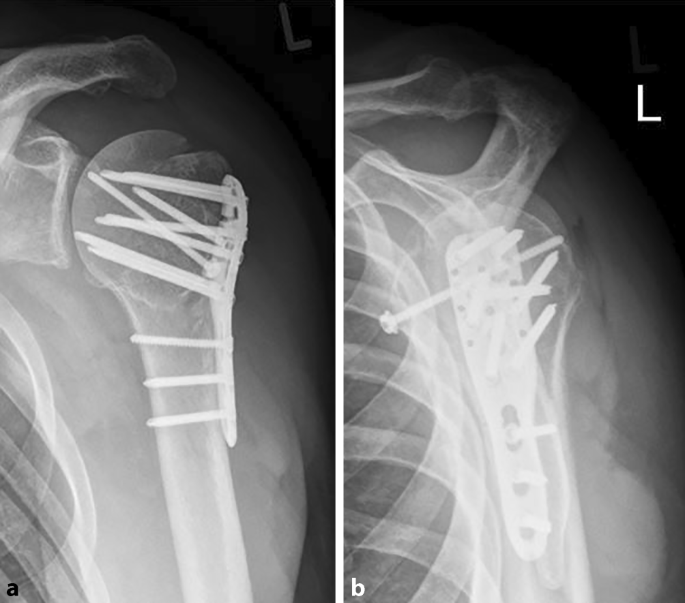

Before downloading you can preview any. Right image:the fracture has healed six months later. Head, neck, surgical neck, greater tubercle, lesser tubercle, intertubercular groove. In proximal humerus fractures, the severity is often described by how many of the.